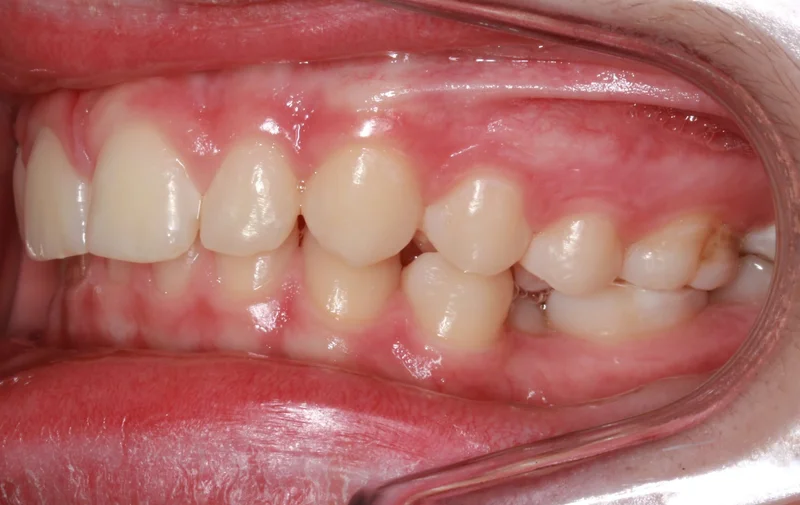

Left Side Bite

Left Side Bite - After Treatment

After